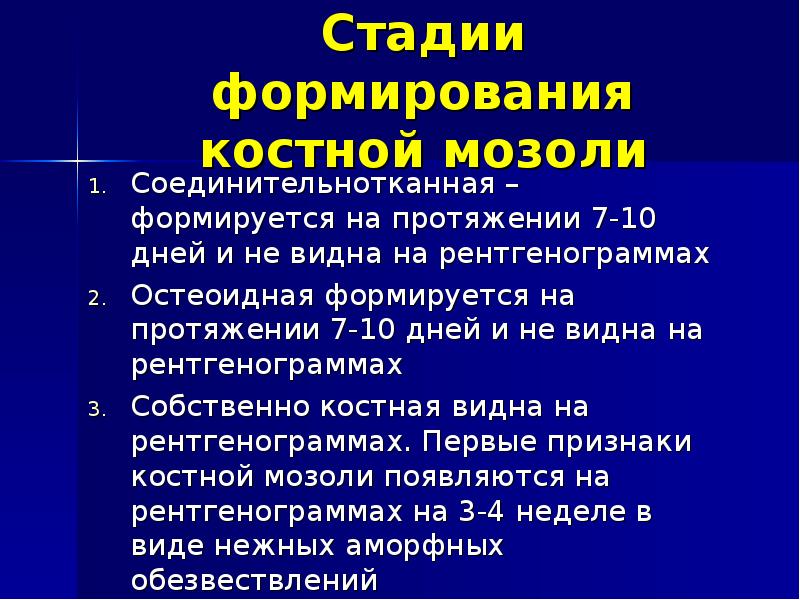

32. Стадии формирования костной мозоли

1.

2.

3.

Соединительнотканная – формируется

на протяжении 7-10 дней и не видна на

рентгенограммах

Остеоидная формируется на протяжении

7-10 дней и не видна на

рентгенограммах

Собственно костная видна на

рентгенограммах. Первые признаки

костной мозоли появляются на

рентгенограммах на 3-4 неделе в виде

нежных аморфных обезвествлений

Описание слайда:

Стадии формирования костной мозоли

Соединительнотканная – формируется на протяжении 7-10 дней и не видна на рентгенограммах

Остеоидная формируется на протяжении 7-10 дней и не видна на рентгенограммах

Собственно костная видна на рентгенограммах. Первые признаки костной мозоли появляются на рентгенограммах на 3-4 неделе в виде нежных аморфных обезвествлений